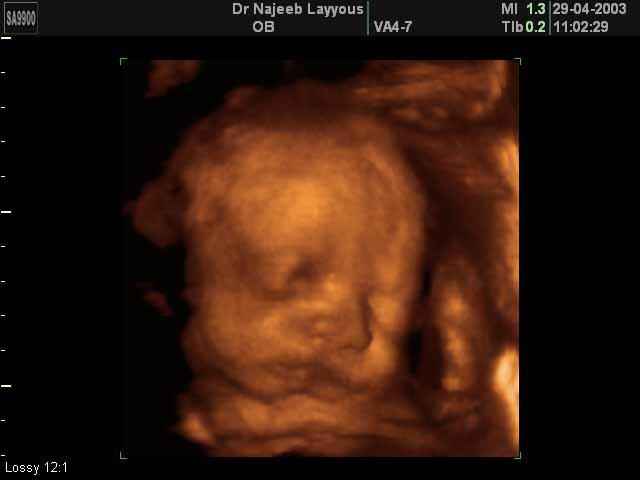

3D Fetal Face Ultrasound Scan Photos